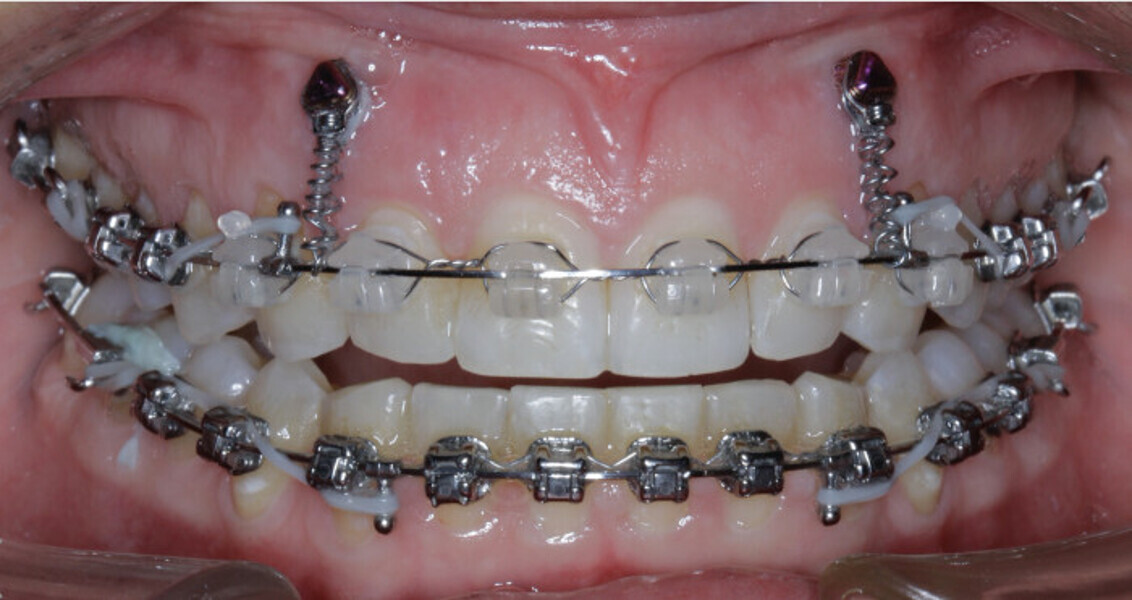

New Age orthodontics and orthopaedics with temporary anchorage devices